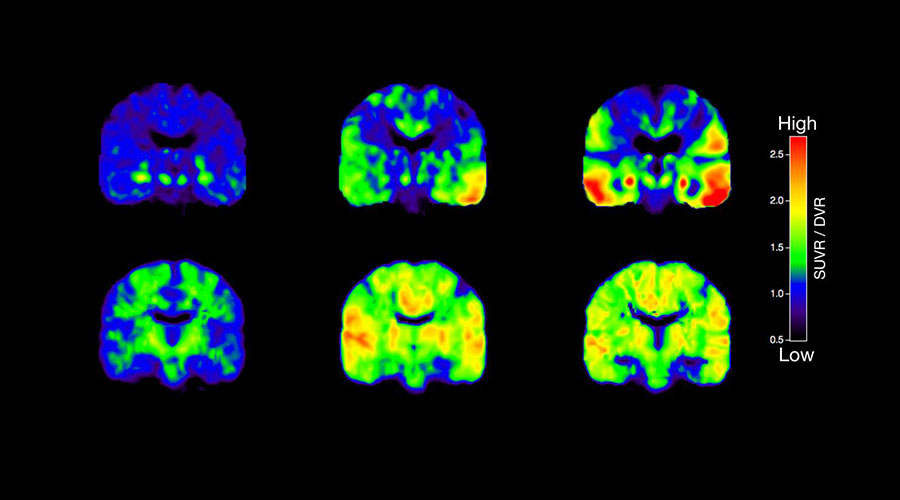

Таким образом, на разрезах, взятых в зависимости от глубины дыхания пациента; Секция справа (как показано на рисунке выше) не является продолжением секции слева, и круглое белое поражение легкого было пропущено, потому что пациент не дышал регулярно. Следовательно, следующий сделанный разрез может фактически не быть продолжением предыдущей области легкого, и если там есть поражение, оно будет пропущено с помощью классического метода томографии.